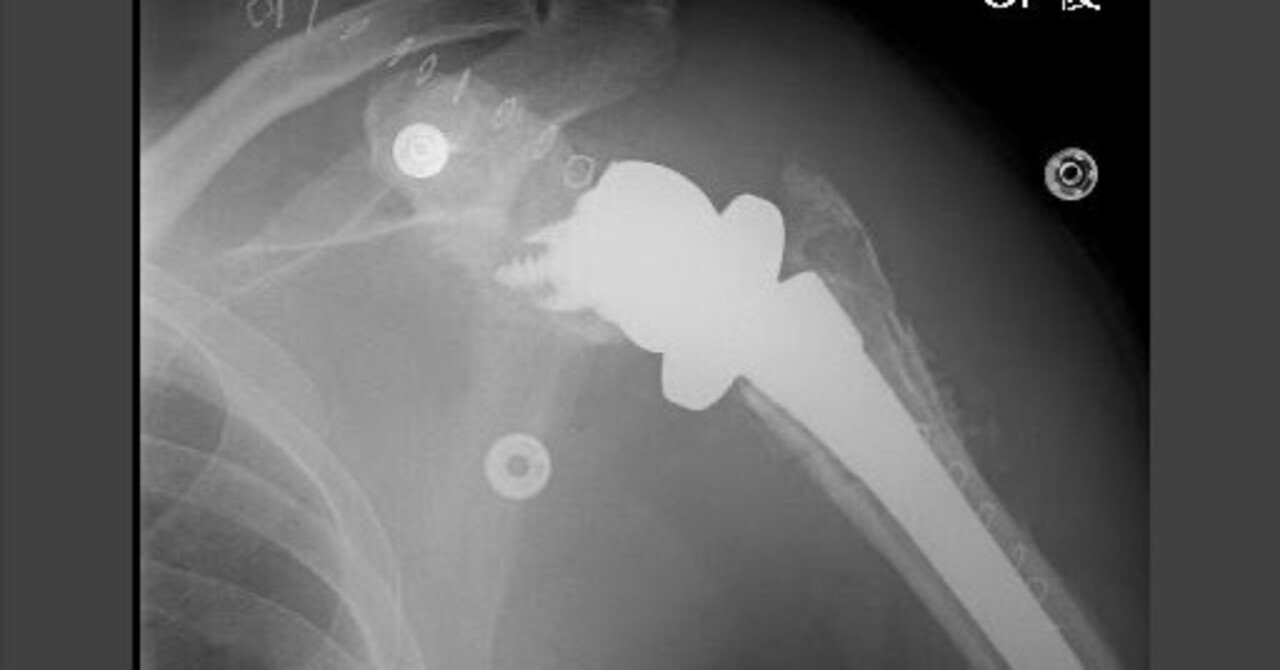

HOT ! 人工肩関節置換術 : HHR・TSA・RSA 人工肩関節置換術 HHR・TSA・RSA|動画ライブラリ

人工肩関節置換術 : HHR・TSA・RSA 人工肩関節置換術 HHR・TSA・RSA|動画ライブラリの詳細情報

人工肩関節置換術 HHR・TSA・RSA|動画ライブラリ。人工肩関節置換術: HHR・TSA・RSA (整形外科SURGICAL TECHNIQUE BOOKS。TSA & RSA Expert | e-casebook。「人工肩関節置換術 : HHR・TSA・RSA」菅谷 啓之 / 菅谷 啓之定価: ¥ 13000#菅谷啓之 #菅谷_啓之 #菅谷啓之 #菅谷_啓之 #本 #自然/医療・薬学・健康書き込み、マーカー等はないかと思いますが、見落としがありましたらお許しください。人工肩関節置換術: HHR・TSA・RSA (整形外科SURGICAL TECHNIQUE BOOKS。

• 人工肩関節置換術 HHR・TSA・RSA|動画ライブラリ

• 人工肩関節置換術: HHR・TSA・RSA (整形外科SURGICAL TECHNIQUE BOOKS

• TSA & RSA Expert | e-casebook